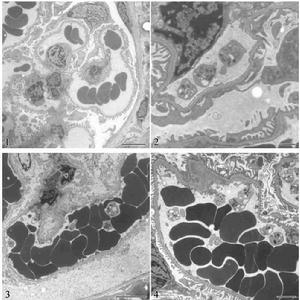

2、病理

毛細支氣管上皮細胞壞死和周圍淋巴細胞浸潤,黏膜下充血、水腫和腺體增生、粘液分泌增多。毛細支氣管狹窄甚至堵塞,導致肺氣腫和肺部不張,出現通氣和換氣功能障礙。